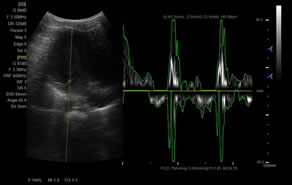

> 脈沖頻譜多普勒成像(PW)

廣泛適用于腹部、婦產(chǎn)科、心臟、小器官、乳腺、肌骨及外周血管等諸多方面的診查,讓您在臨床超聲診斷應(yīng)用領(lǐng)域得心應(yīng)手,綻放異彩。